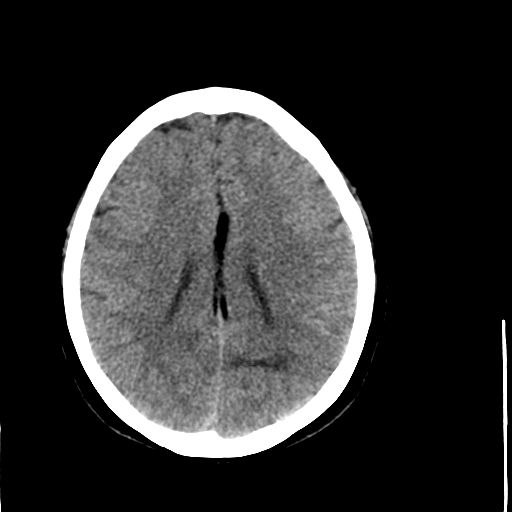

病人资料:女,57岁,反复头痛6年余,无恶心、呕吐等症状,体查:bp180/100mmhg。

中线脂肪瘤

胼胝体发育不良并脂肪瘤形成,脂肪瘤形成是因,胼胝体发育不良是果。如果正规些应该是中线脂肪瘤并胼胝体发育不良!

典型中线脂肪瘤

胼胝体发育不良

中线脂肪瘤并胼胝体发育不良。